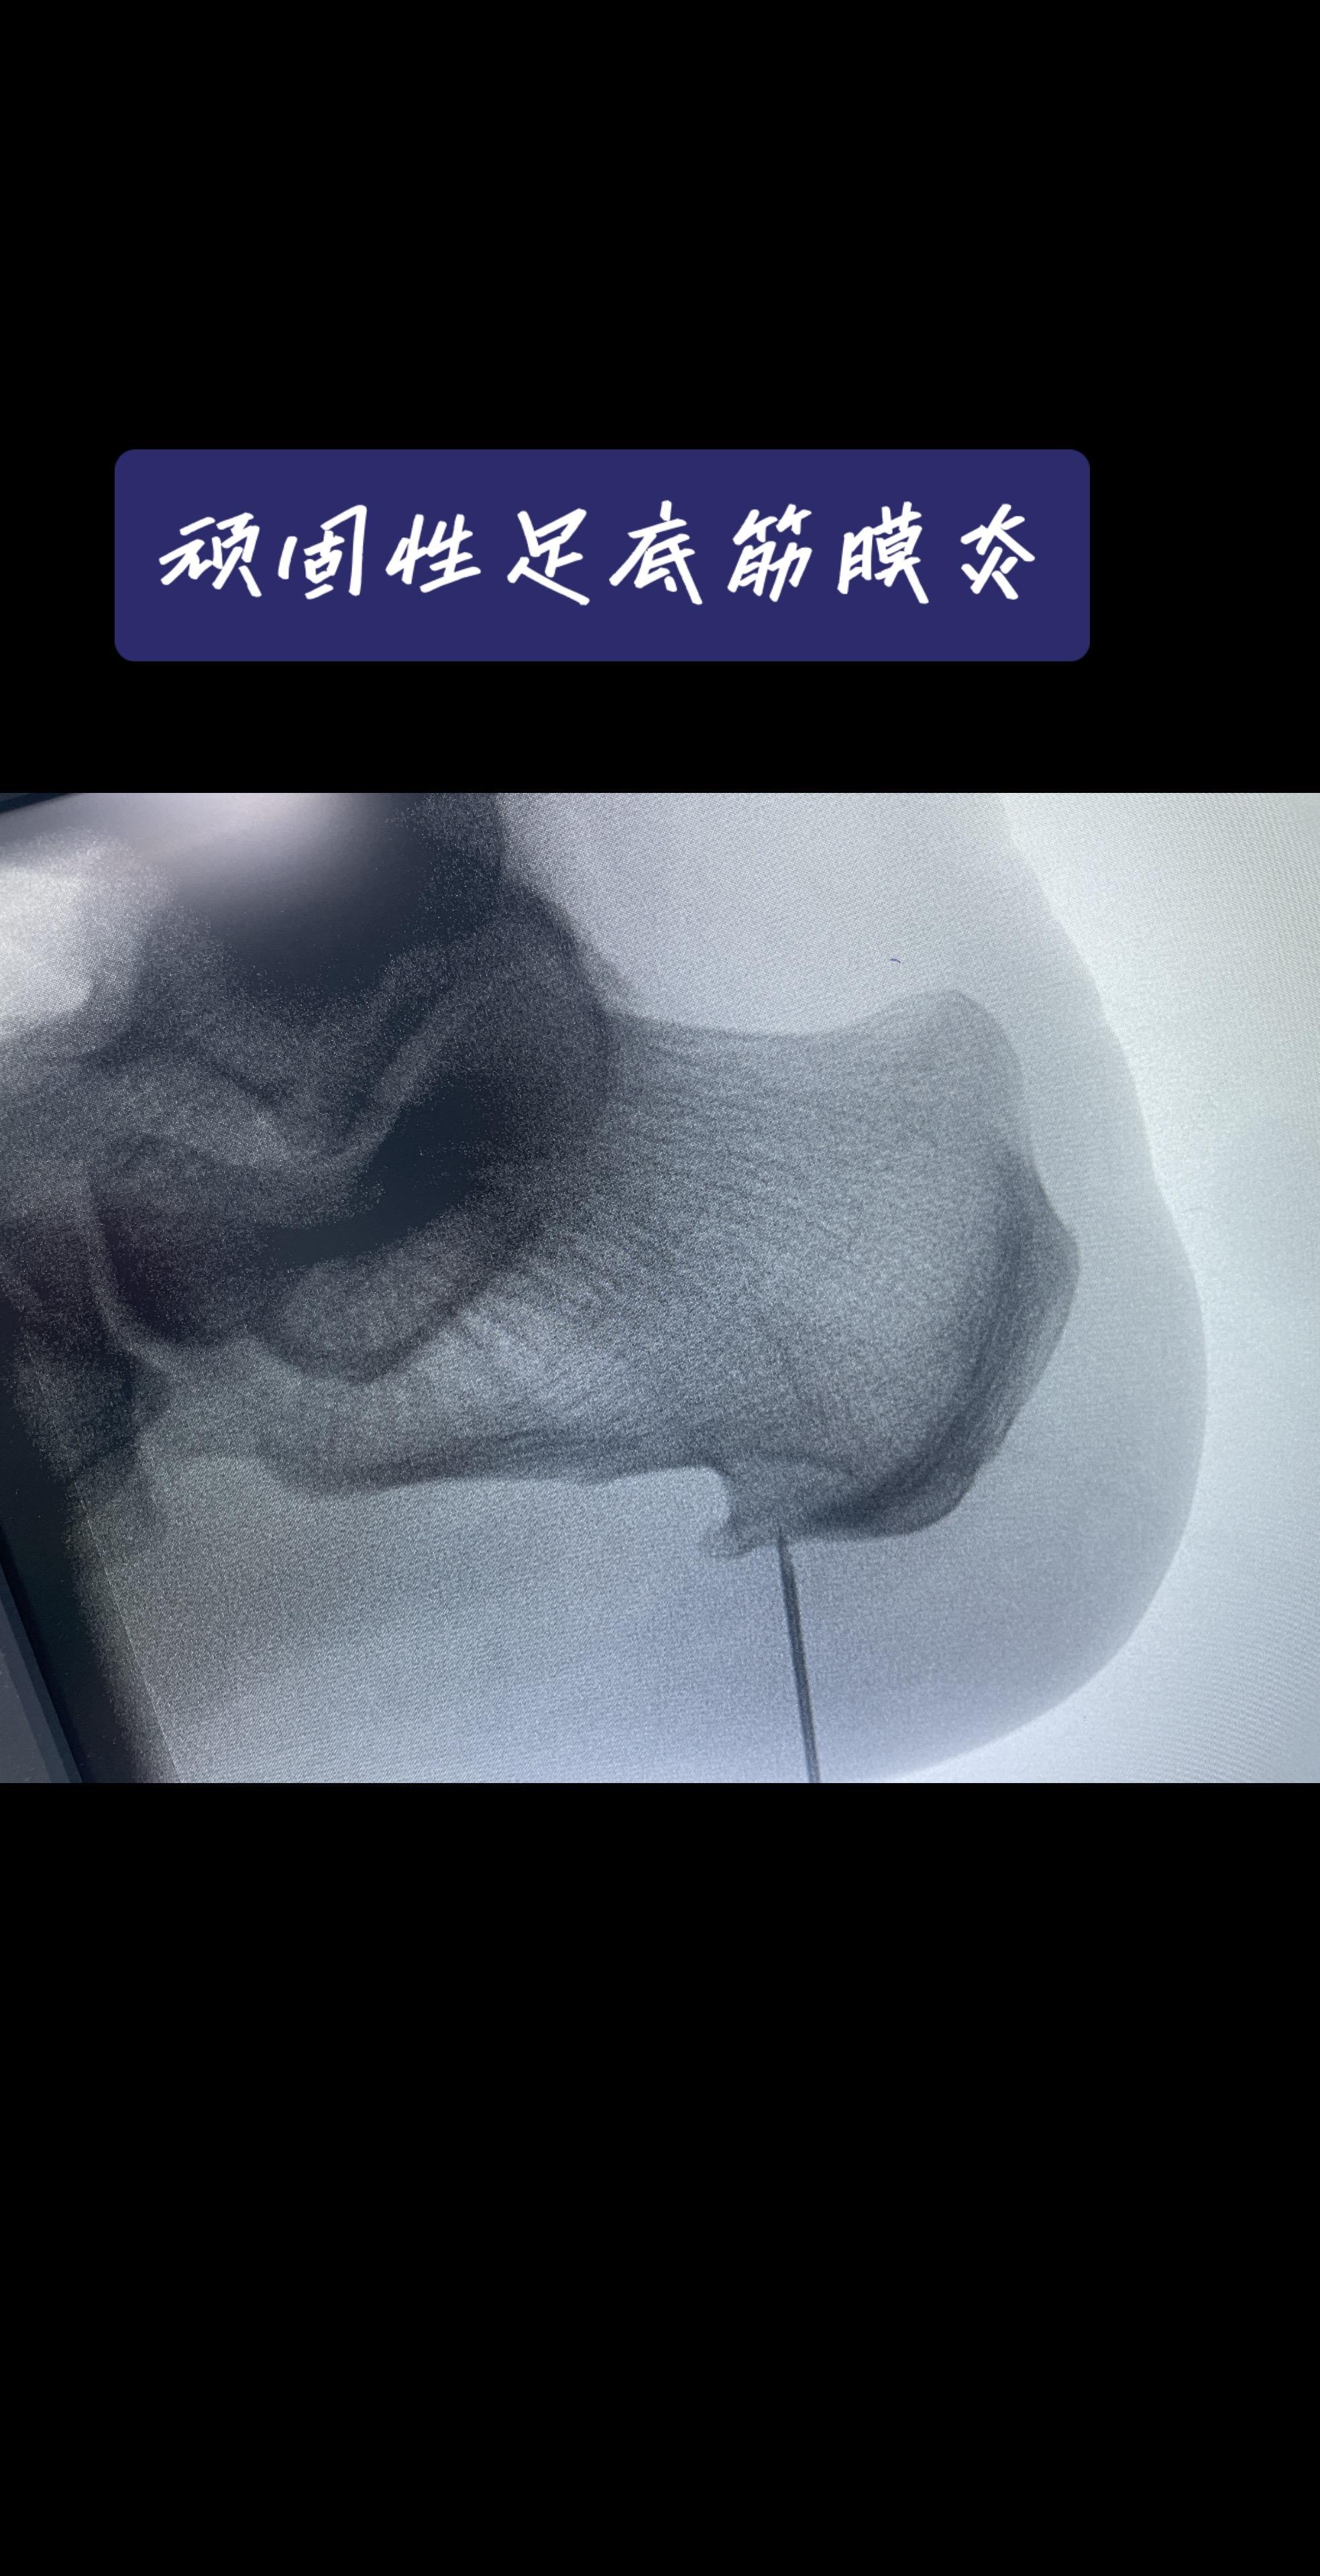

脚后跟像踩针?一走路就钻心疼?对于忍了好几年,试遍各种方法都没用的‘顽固分子’,我们怎么办?——关节镜下的‘筋膜松解术’,创伤小、恢复快,告别‘起步痛’!